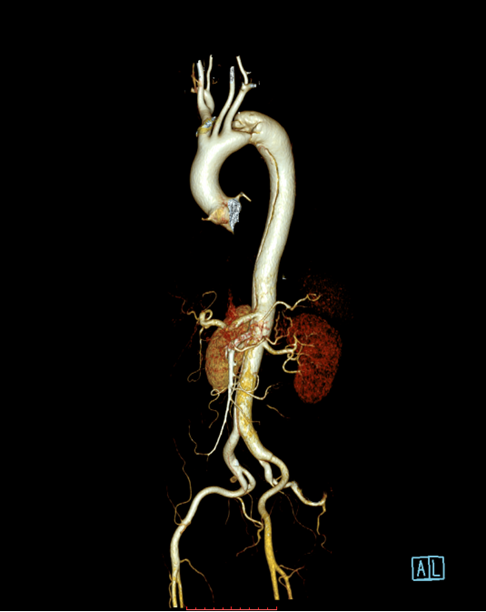

患者以“突发胸背部疼痛1月余”为主诉急诊入住中南大学湘雅二医院血管外科,入院后经过CTA确诊为“主动脉夹层”,夹层第一破口紧邻左锁骨下动脉,且左锁骨下动脉起始部呈局限性夹层样改变,胸主动脉真腔全程受压,病情十分危重,患者疼痛难忍!

经过仔细测量及讨论,根据患者夹层真腔受压严重、近端锚定区不足,左锁骨下动脉累及到血管根部以及病情比较危重的特点,舒畅教授决定使用目前已开展的临床试验研究项目(PATENCY study/NCT03767777)“先健新型主动脉弓烟囱支架”,该研究是先健科技公司与舒畅教授合作研发的新型主动脉弓烟囱支架,对于累及弓上分支的主动脉夹层、且病情比较紧急的患者具有明显的优势!

术中通过DSA造影显示:主动脉夹层破口位于左锁骨下动脉近端,真腔压闭!舒畅教授为患者完美的实施TEVAR+左锁骨下动脉裙边烟囱支架置入术,手术过程非常顺利,胸主动脉支架释放良好,患者的主动脉夹层破口封闭良好,真腔打开良好,左锁骨下动脉释放的裙边支架血流通畅,没有内漏发生。